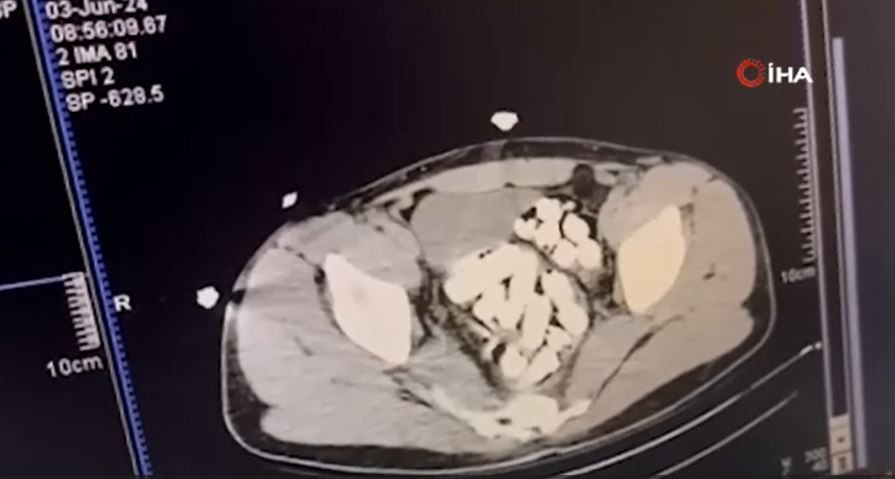

Şüpheliler pasaport kontrolünden geçirildikten sonra gözaltına alındı. Ardından hastaneye sevk edilen iki şüphelinin röntgenleri çekildi.

Midelerinden 1 kilo 415 gram esrar maddesi çıktı

İki şüphelinin midelerinden toplamda 122 adet kapsül halinde 1 kilo 415 gram esrar maddesi çıktı. Yakalanan şüpheliler uyuşturucu madde ticareti suçundan sevk edildikleri adli makamlarca tutuklanarak cezaevine gönderildi.